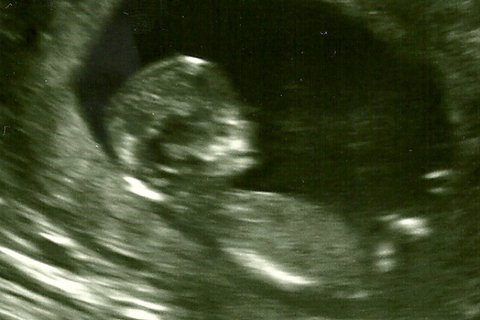

The state of Texas, which was subject to a landmark Supreme Court ruling today, is one of a handful of states requiring not only that abortion providers perform an ultrasound, but that they both…

“I held my tongue as she told me, ‘Son, fear is the heart of love.’ So I never went back.” – Death Cab for Cutie, from “I Will Follow You into the Dark” (2005) Ahead of today’s historic Supreme Court…